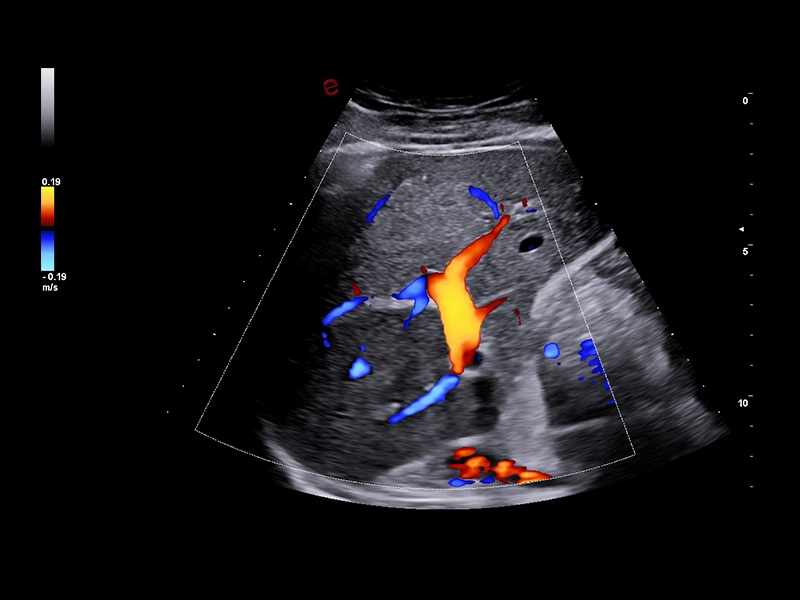

MyLab™9 Platform - XFlow Doppler enhancement in liver vascularization

MyLab™9 Platform - XFlow Doppler enhancement in liver vascularization